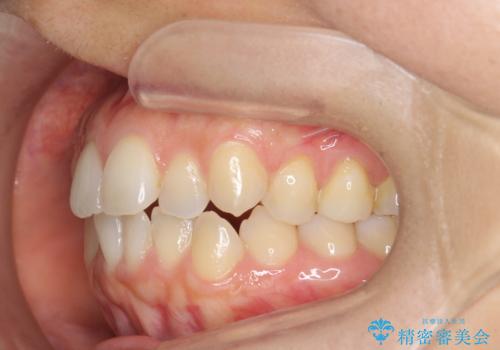

前歯のガタつきをマウスピースで治したい!

- 気になる前歯のガタつきをマウスピースで治療したいと希望され来院されました。

当日に矯正検査を行い、骨格・歯に問題がないことを確認しマウスピースによる矯正治療を進めます。

IPRを前歯部に少量行うことで、非抜歯でも前歯が外に飛び出さない仕上がりを達成できました。